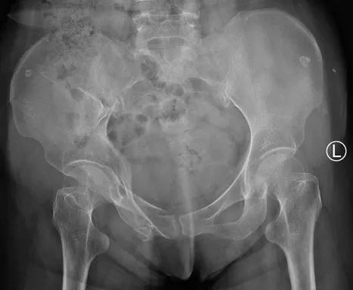

该患者是一名71岁老年女性,滑倒摔伤致右髋部疼痛伴活动受限10天,到我院急诊就诊。影像学检查诊断为骨盆骨折(Young & Burgess分型为LC-2),重度骨质疏松,收入院准备手术治疗。

图丨患者术前影像

老年人发生骨盆骨折大多是因为低能量外伤结合患有骨质疏松而造成的脆性骨盆骨折,随着中国老龄化人口结构的加剧,脆性骨盆骨折发生率逐年升高,由于这种骨折的高并发症率和致死率,逐渐成为威胁老年人健康和寿命的又一个重要病因。